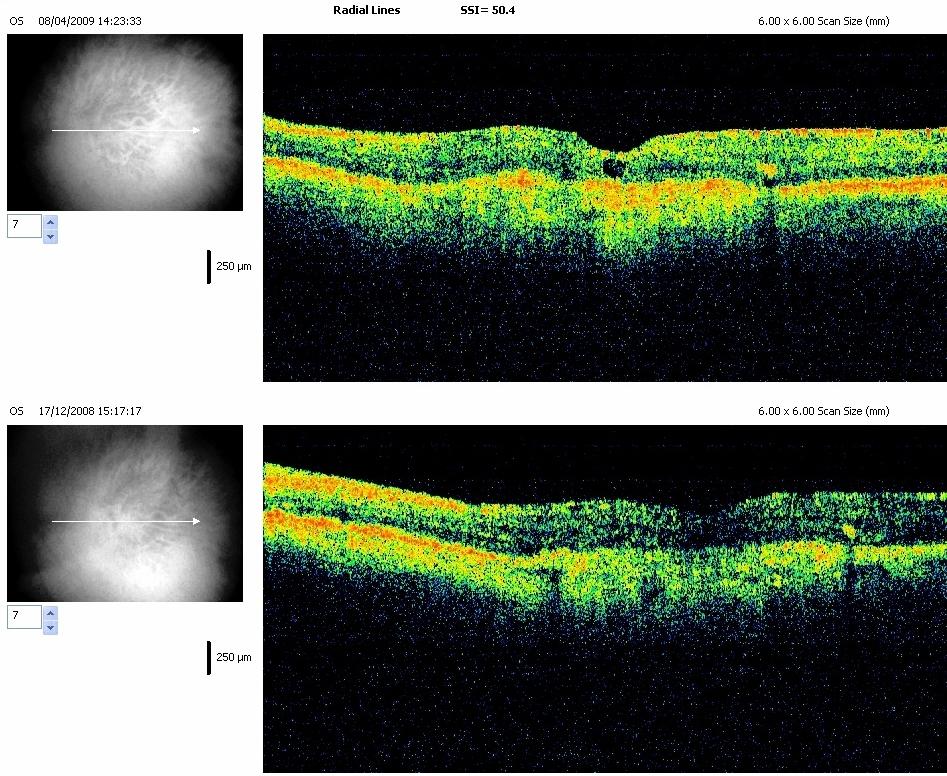

Chaque dossier correspond à un cas dans lequel peuvent se trouver plusieurs examens à des dates différentes.

Path: /3101-20081107-01/08-04-2009/slides